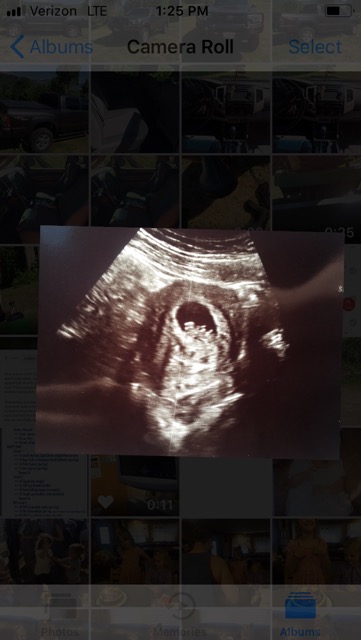

Ramzi theory?

What do you think? This was when I was 8wks, heart rate was 144! Now 150 at almost 11 weeks